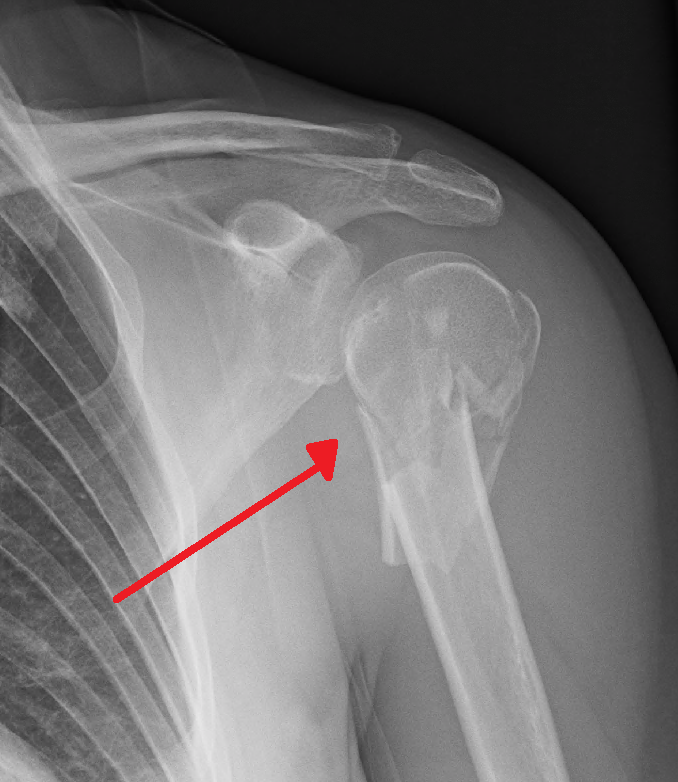

humeral fractures

humeral neck fractures

proximal humeral fracture

clavicle fracture